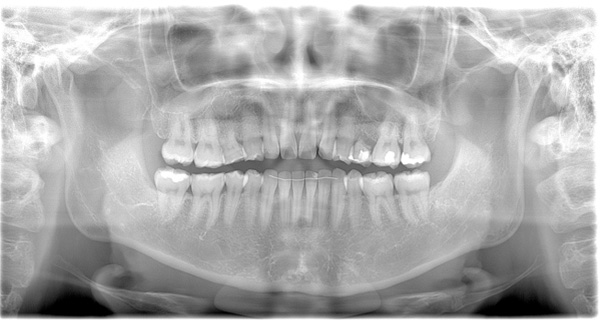

| 年代・性別 | 50代 女性 |

| 主訴 | 左上のブリッジがグラグラして外れそう |

| 治療期間 | 約18ヶ月 |

| 費用 | 1,600,000円 |

| 治療内容 | インプラント、骨造成、サイナスリフト、セラミック修復 |

| 治療に伴うリスク | インプラント周囲炎 セラミックの破折、脱離 |